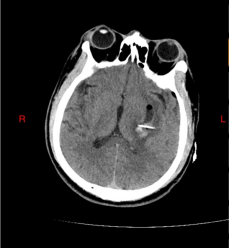

术中导航:C臂CT三维成像锁定穿刺路径

可视导管:镜下避开血管,直达血肿中心

术后对比:血肿清除率达95%,脑组织压迫解除